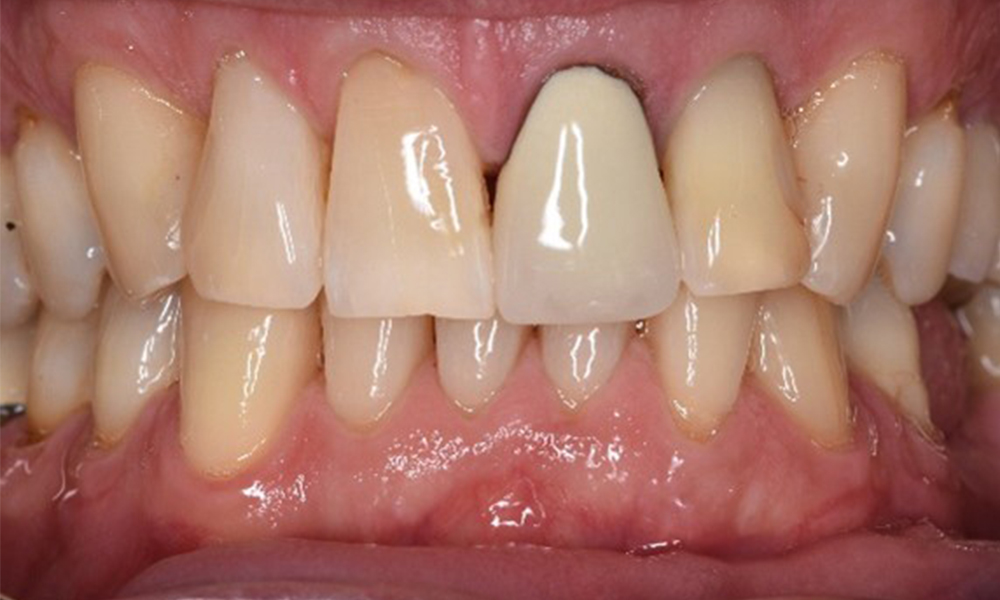

The endocarditis patient with active caries lesions

The patient is 39 years old and has previously undergone aortic valve replacement due to valve failure and endocarditis. ASS 100 is taken regularly as an anticoagulant. In terms of lifestyle, the patient’s diet is classified as caries-promoting due to the regular consumption of sugary foods and the fact that six to seven meals are consumed daily. The patient’s oral health indicates a moderate risk of caries, with active lesions. The risk of periodontitis is low, but gingivitis is present. The following recommendations are made for prophylactic treatment. more